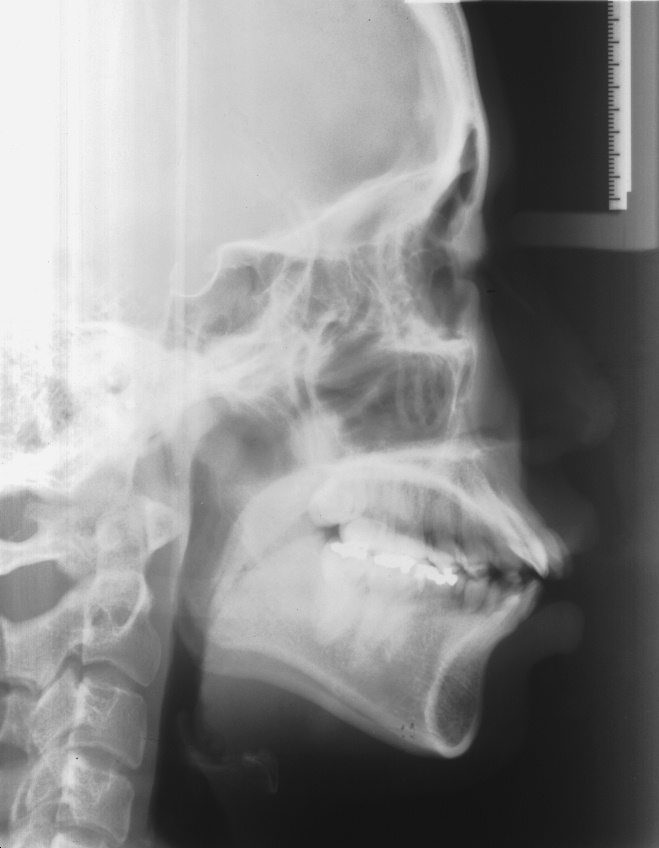

치료 후 사진입니다.